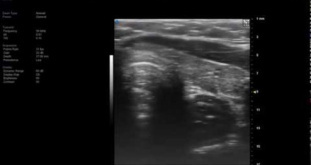

SII HFL38 - Internal Jugular Vein 8464